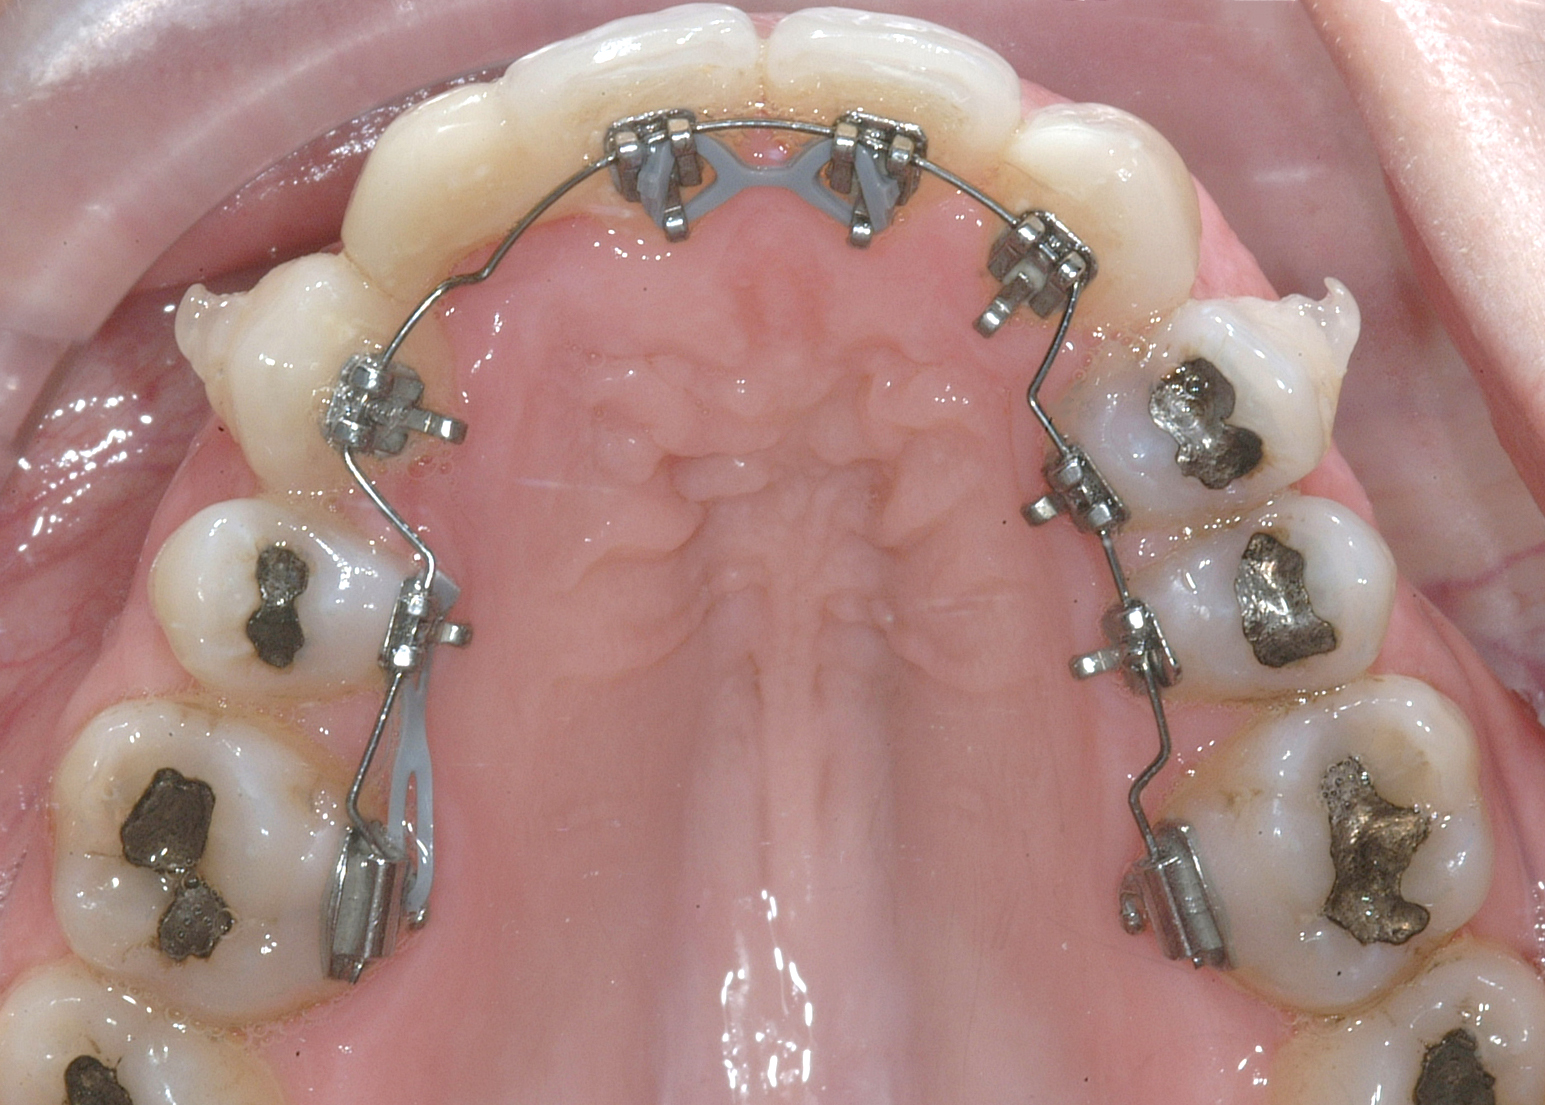

Il protocollo terapeutico ha previsto l’estrazione del primo premolare inferiore sinistro (3.4) e del primo superiore destro (1.4), l’applicazione di una apparecchiatura fissa linguale 2D e di una meccanica asimmetrica di ancoraggio e movimento ortodontico a entrambe le arcate (Figure 3a-b).

Il trattamento è iniziato con l’estrazione dei due premolari in unica seduta in anestesia locale e l’applicazione simultanea, dopo una settimana, della apparecchiatura linguale inferiore e superiore, non essendoci problemi di overbite e potenziali interferenze in occlusione tra l’apparecchiatura superiore e i frontali inferiori. All’arcata superiore è stata effettuata una iniziale chiusura dello spazio estrattivo con forze molto leggere in ancoraggio medio su arco .014” Nichel-Titanio e successivamente .016” Nichel-Titanio, bondato in prima fase per maggior stabilità direttamente sulla superficie mesiale di 2.4.